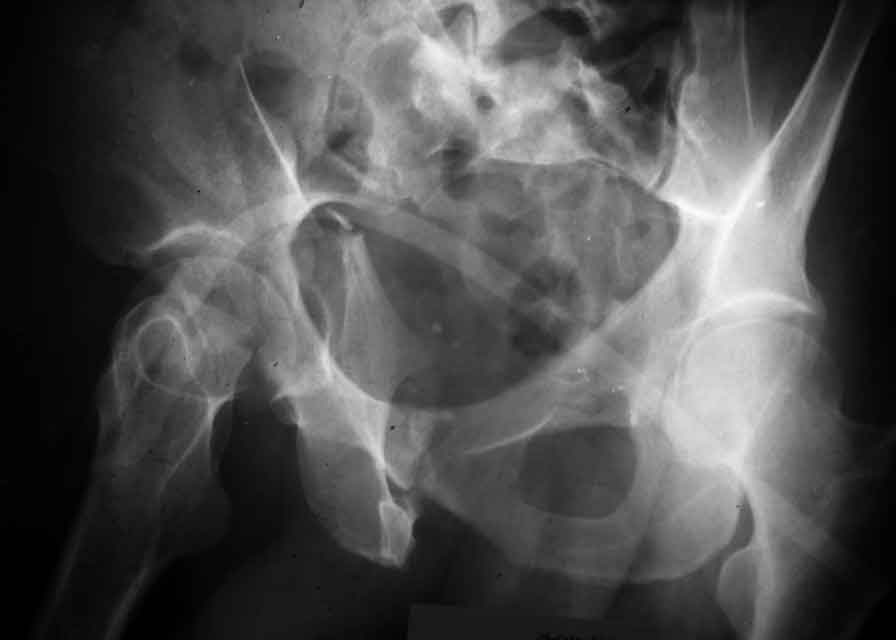

Dear Sir it looks quite difficult classify this fracture because the iliac view is not so clear.

In my opinion it is a column fracture because the obturator foramen is interrupted. There is a fracture of the posterior wall. If we assume the ap view as an iliac view it could be an anterior comun fracture plus posterior wall. It is difficult also to judge the head of the femur.

From the x rays it appears like a bicolumnar fracture with iliac extension (AO C1).

I am sending another iliac view, and a marked version of the AP I already sent. In this AP, the

proximal part of the greater sciatic notch as well as the distal parts of the ilioischial and iliopubic lines are marked with a grey interrupted line. A white interrupted line marks what could be an exit through the obturator foramen, or so I assume.